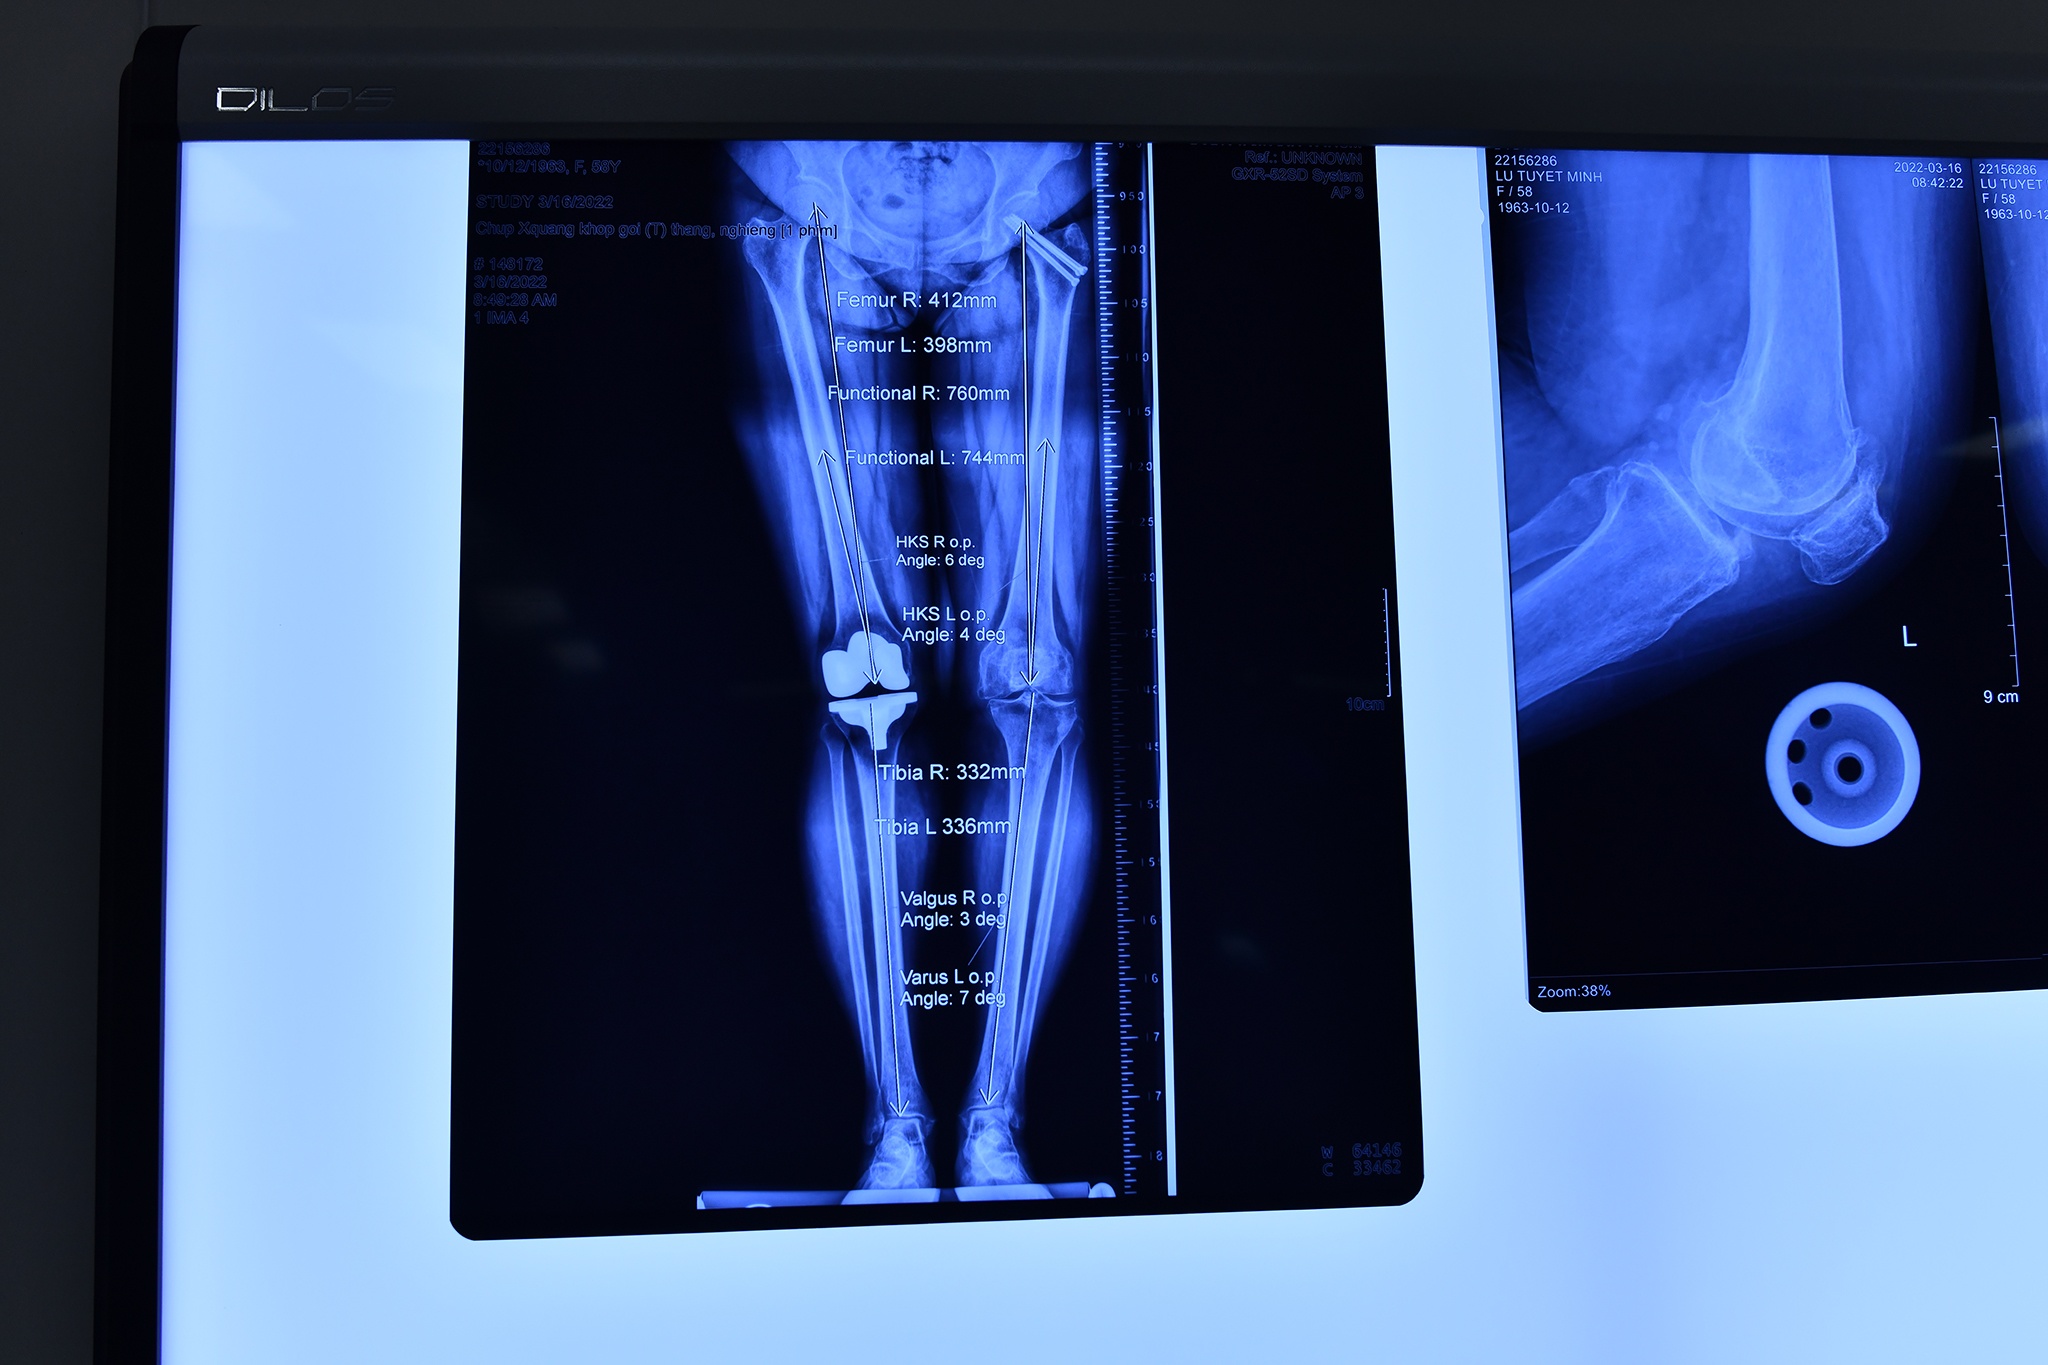

Trước ca mổ, các bác sĩ từ nhiều chuyên khoa của Bệnh viện Đa khoa Tâm Anh như Chấn thương chỉnh hình, Nội tổng hợp, Gây mê hồi sức… cùng hội chẩn. Họ xem lại một lần nữa hình ảnh X-quang và MRI của bệnh nhân, xác định khớp gối trái bị thoái hóa toàn phần.

Phần mềm kỹ thuật số TraumaCad chuyên dụng để lập trình kế hoạch trước mổ đã phân tích và cho các thông số chính xác về hệ xương khớp của người bệnh. Phần trục chân bị lệch (cong) khoảng 3 độ - nguyên nhân khiến người bệnh cảm thấy rất đau khi di chuyển. Cũng nhờ phần mềm TraumaCad, kế hoạch mổ chi tiết về các lát cắt, vị trí đặt khớp nhân tạo… được lập ra rất cụ thể, đảm bảo khớp gối nhân tạo sẽ làm thẳng trục chân cho người bệnh sau phẫu thuật.